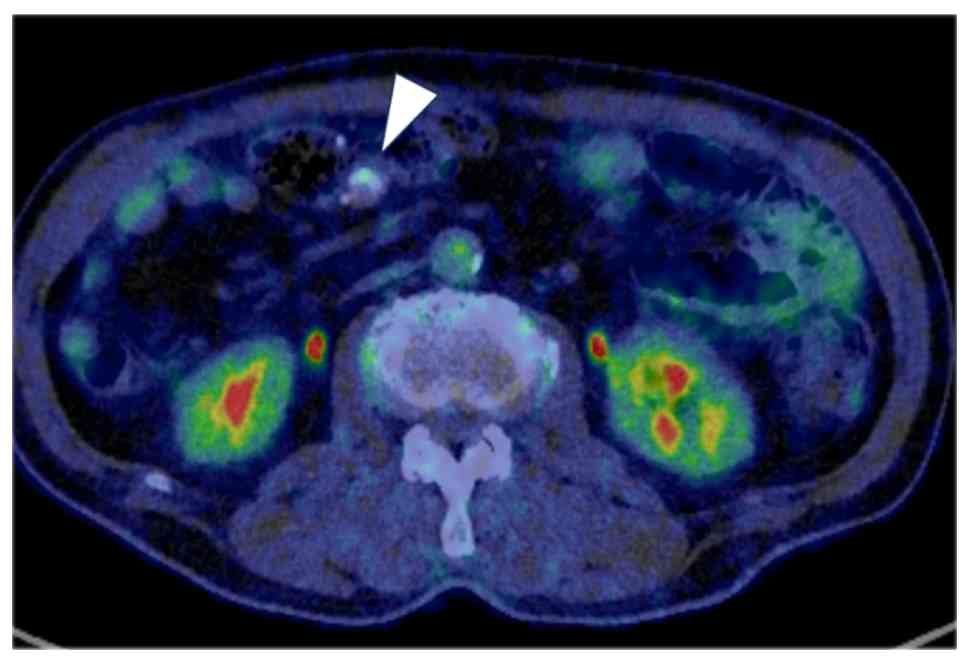

PET-CT findings. PET-CT showed no

significant fluorodeoxyglucose uptake in the lesion (arrowhead).

PET-CT, positron emission tomography-computed tomography.

Figure 3

PET-CT findings. PET-CT showed no significant fluorodeoxyglucose uptake in the lesion (arrowhead). PET-CT, positron emission tomography-computed tomography.